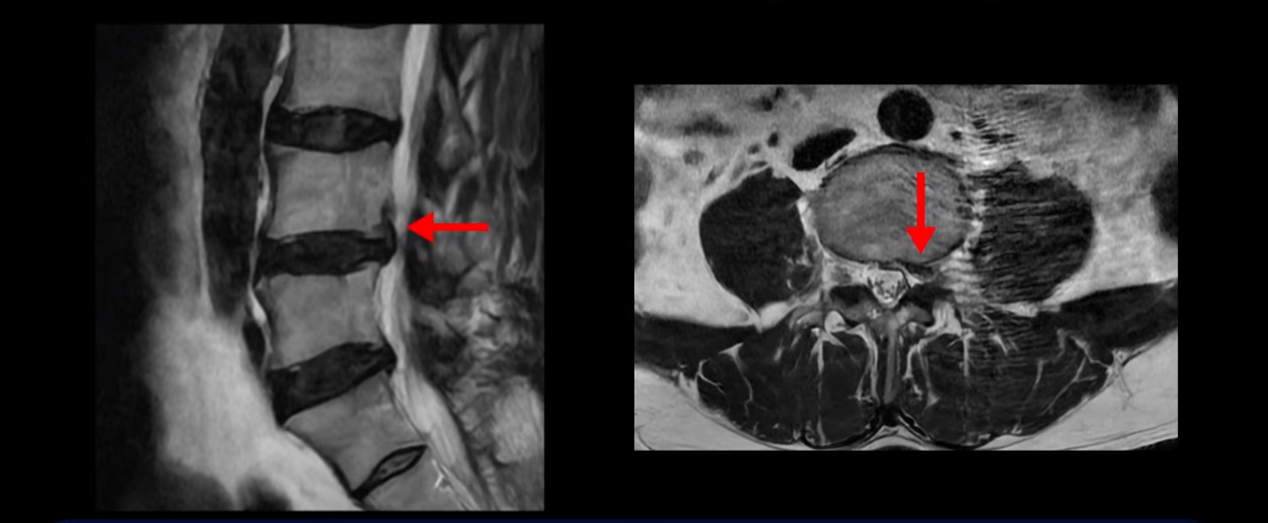

이분 MRI를 보면 허리 세 마디 정도의 퇴행성 디스크가 있고

4번 5번 마디에는 중심성 협착이 있습니다.

후관절과 황색인대가 두꺼워져 있어서 척추관이 좁아져 있습니다.

하지만 이분의 갑작스러운 통증을 일으키는 원인은 4번 5번에 발생한 디스크 파열입니다.

이분은 왼쪽 무릎 아래로 본인 표현으로는 다리를 잘라 버리고 싶다고 할 정도의 심한 통증이 있는데 보통 이런 표현은 디스크 파열이 발생했을 때 많이 사용하는 표현입니다. 이분 4번 5번 디스크를 자세히 보면 왼쪽으로 파열되어 밀려 올라간 디스크 수핵을 볼 수 있습니다.

옆에서도 보이지만 단면에서도 왼쪽으로 심하게 밀려나온 수핵이 잘 보입니다.